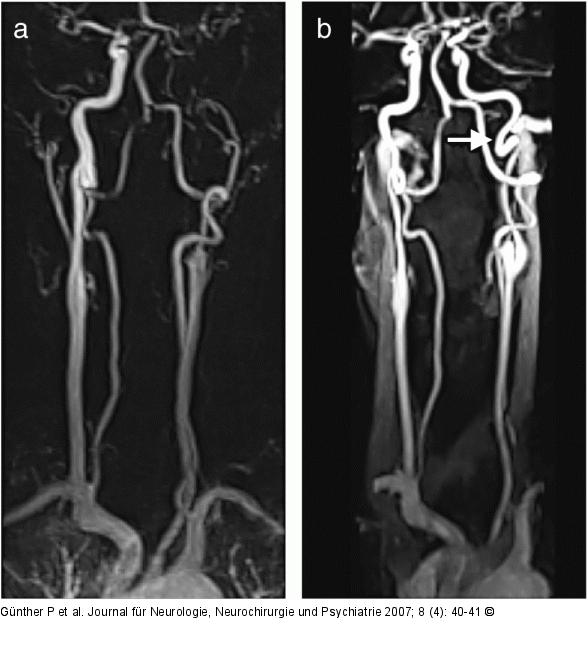

Abbildung 2: Arteria carotis - Dissektion (a) Kontrastmittelgestützte MR-Angiographie einer 37jährigen Patientin mit Dissektion und Verschluß der linken A. carotis interna (ACI) unter jahrelanger Therapie mit D-Penizillamin bei Morbus Wilson. Die Verlaufskontrolle nach einem Jahr (b) zeigt die Rekanalisation des Gefäßes und zusätzlich eine Schleife (Coiling) im Bereich der Schädelbasis (Pfeil). |

Abbildung 2: Arteria carotis - Dissektion

(a) Kontrastmittelgestützte MR-Angiographie einer 37jährigen Patientin mit Dissektion und Verschluß der linken A. carotis interna (ACI) unter jahrelanger Therapie mit D-Penizillamin bei Morbus Wilson. Die Verlaufskontrolle nach einem Jahr (b) zeigt die Rekanalisation des Gefäßes und zusätzlich eine Schleife (Coiling) im Bereich der Schädelbasis (Pfeil). |